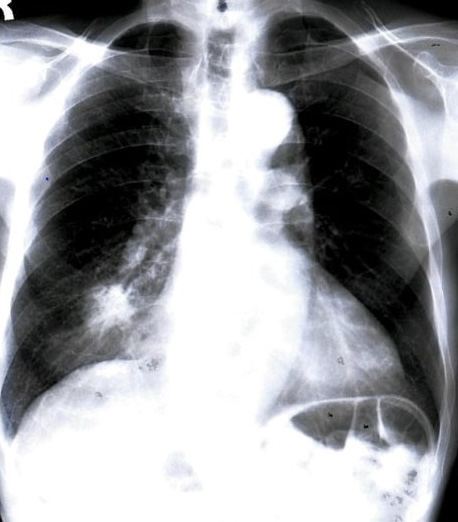

An elderly patient with recurrent pneumonia ends up with a diagnosis that surprises everyone.

BEING A PUI IS NO FUN PART I